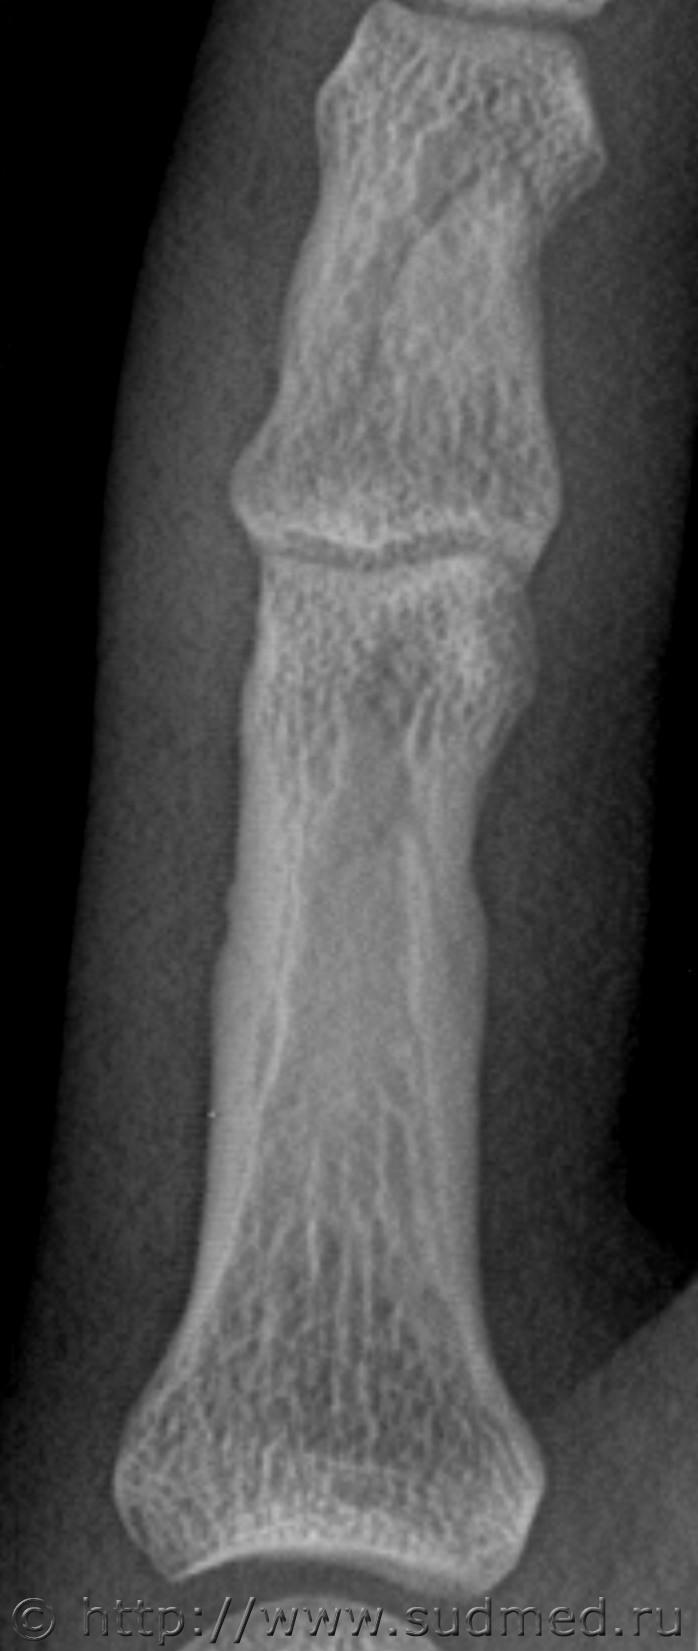

Вот еще один. Немного изменил яркость.

Следующий снимок сделал через 100 дней после травмы, по просьбе экспертов.

Второй снимок, 100 дней после травмы. На рентгеновской пленке.

Заключение: на представленной рентгенограмме 5 пальца левой кисти в 2-х проекциях от (100 после травмы) костно-травматических изменений не выявлено.

Снимок через 100 дней после травмы на рентгеновской пленке остался у экспертов, я его отсканировал перед тем как отдать:

Больше вопросов и предположений вызывает не основная, а средняя фаланга. Если бы она так выглядела через 100 дней после травмы, можно было бы согласиться, что несколько месяцев назад был перелом средней фаланги. Через 13 дней перелом так выглядеть не может. Вероятно, имеется какая-то индивидуальная особенность или когда-то давно (многие месяцы-годы назад) был перелом средней фаланги мизинца. Основная фаланга особых вопросов не вызывает: согласен с рентгенологами по поводу отсутствия достоверных рентгенологических признаков перелома.